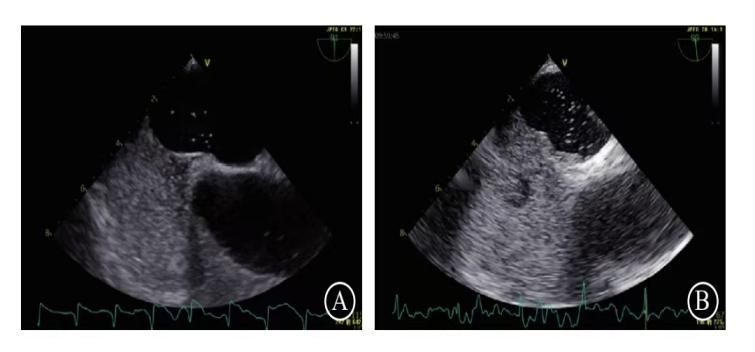

3、介入封堵术:微创闭合“心脏小洞”

介入封堵术通过植入器械永久闭合PFO(见图4),是根治性治疗手段,尤其适用于高危患者。

(2) 手术过程 术前准备:空腹,经食管超声(TEE)明确PFO形态,评估封堵器型号。操作步骤,首先局部麻醉后穿刺股静脉,置入导管至右心房,接下来通过导管将封堵器(双盘状镍钛合金装置)送至PFO处,释放后固定于房间隔两侧,最后超声确认封堵器位置及无残余分流。整个手术时间是30-60分钟,住院1-2天。

图4 PFO封堵器植入术后